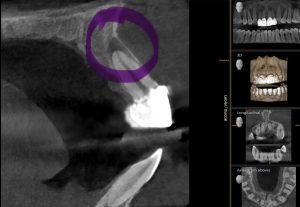

Your dentist will assess the tooth’s condition through X-rays and an oral exam to determine whether extraction is necessary.